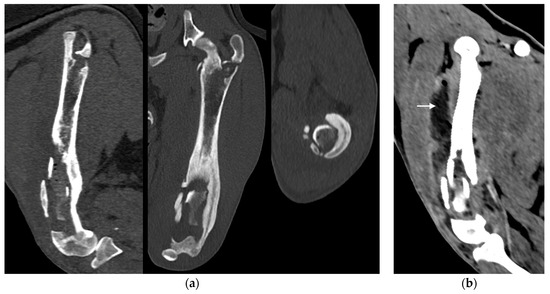

Figure 3. (a) Sagittal, frontal and transverse tomographic images of the metaphysis and the distal-middle third of the femoral diaphysis revealed medullary osteolysis, a wide interruption of the cranio-medial cortical profile with corticomedullar fragment of 4 × 1.4 cm (length × width) medially dislocated at the level of the medullary cavity (bone sequestrum) and an extensive periosteal reaction of the caudo-lateral cortex of the femoral distal diaphysis. (b) Widespread subcutaneous and perifascial abscess lesions were also reported (white arrow).

Under anesthesia, a computed tomography study (CT; Somatom Emotion 16, Siemens, Munich, Germany) of the hind limbs was performed. The tomographic images revealed medullary osteolysis of the metaphysis and the distal-middle third of the femoral diaphysis. In the metaphysis and the distal third of the femoral diaphysis, a bone sequestrum was found: a wide interruption of the cranio-medial cortical profile, with involvement of the femoral trochlea, was observed with corticomedullar fragment of 4 × 1.4 cm (length × width) medially dislocated at the level of the medullary cavity; the fragment was surrounded by a large hypodense halo. Secondary MPL and widespread subcutaneous and perifascial abscess lesions were also reported (Figure 3).